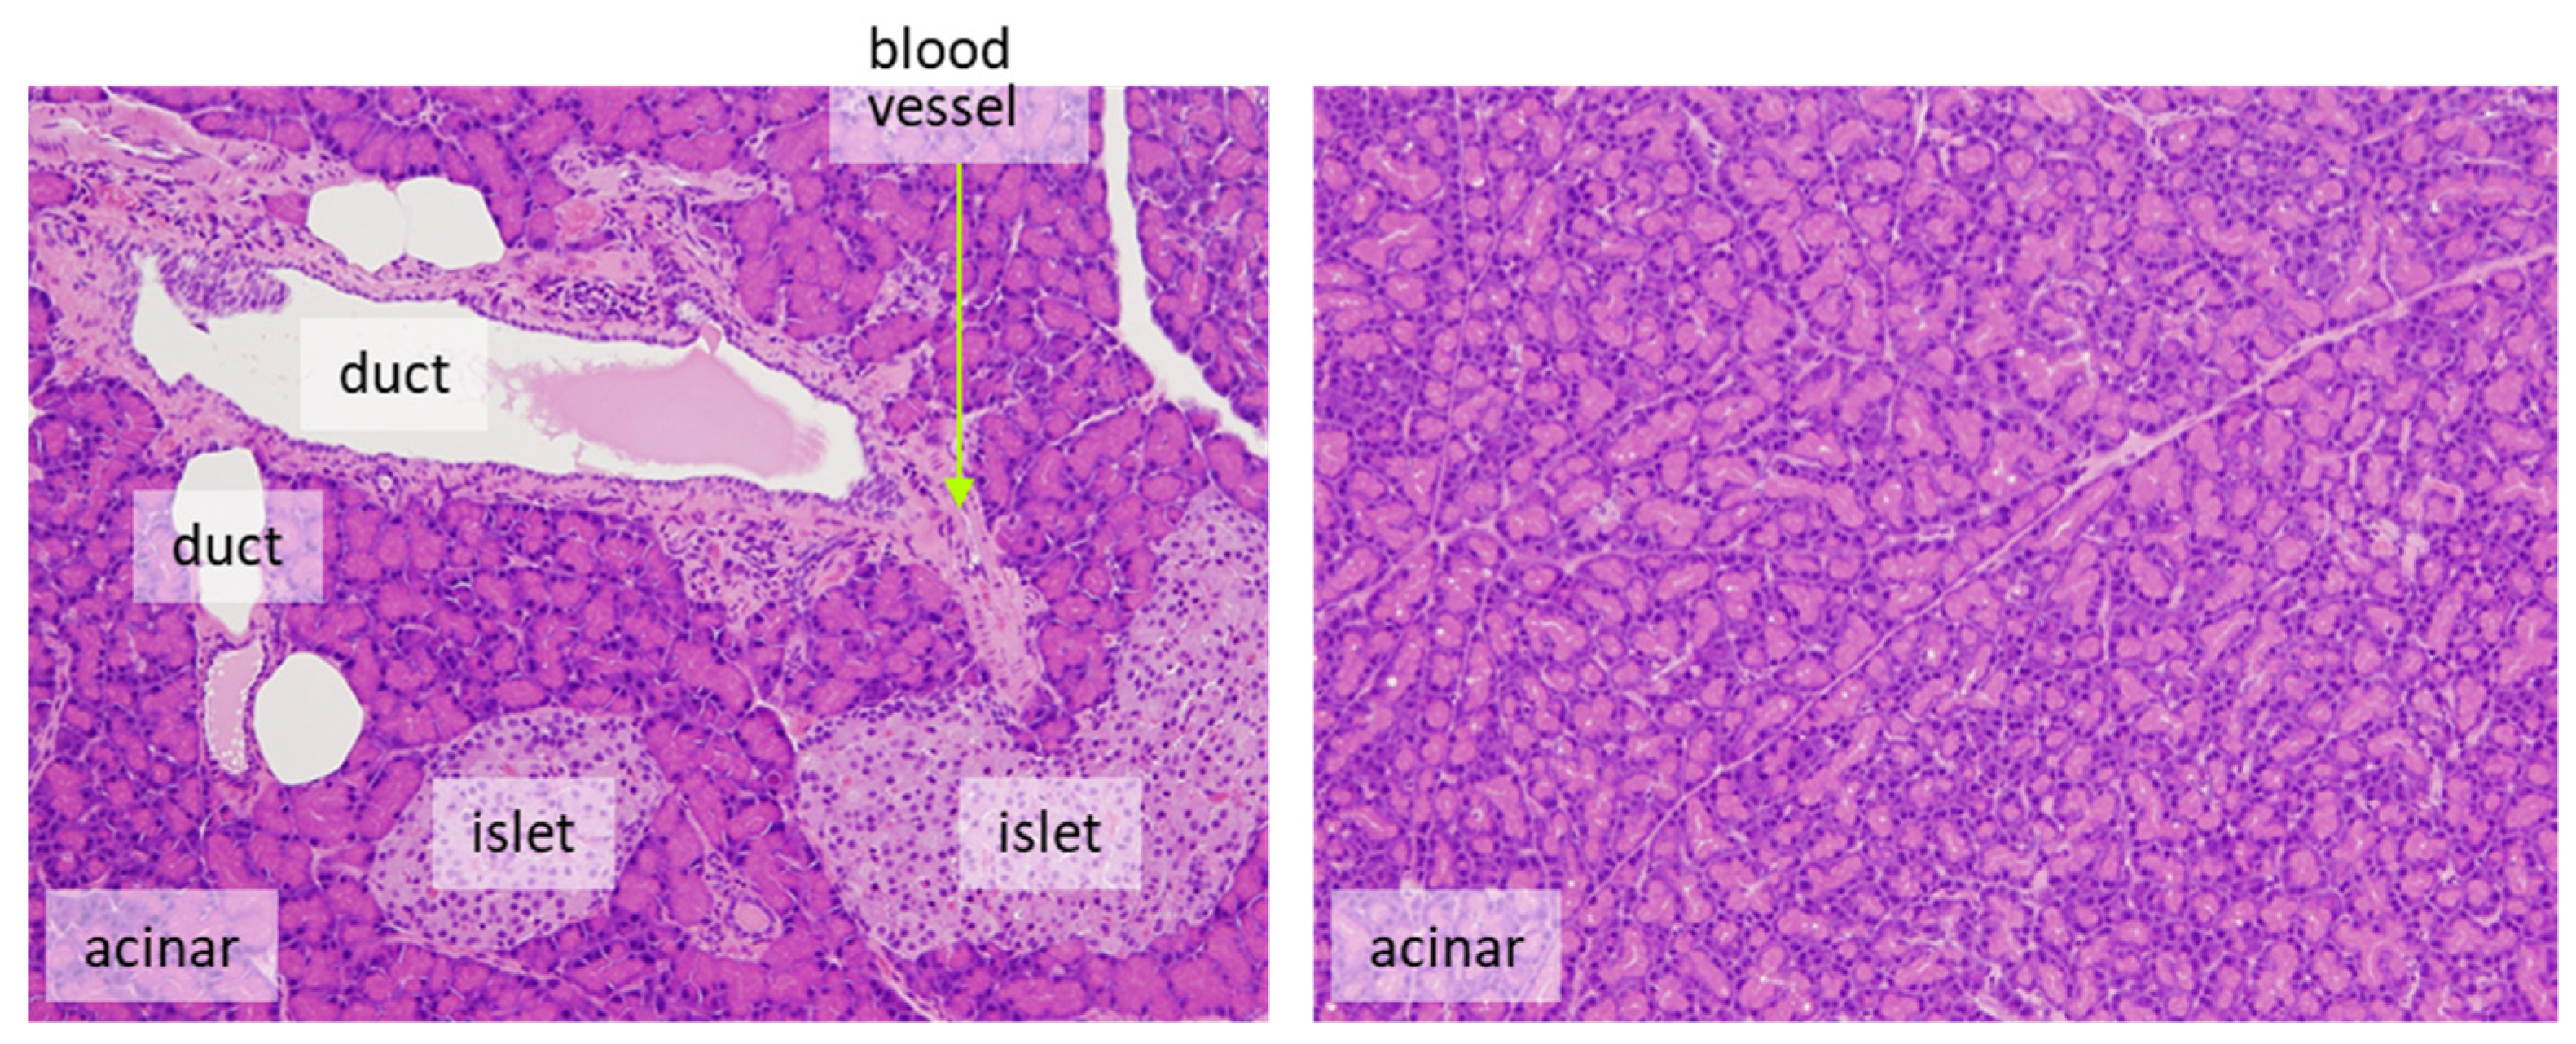

- It is desirable to count only target cells and not multiple cell types. For example, for the evaluation of proliferation in pancreatic endocrine cells, only islet cells should be assessed. Exocrine tumors can arise from ductular or acinar cells. Although the phenomenon is rarely seen in rats, the human pancreas is more likely to develop carcinogenesis from duct-derived cells than from islets or acinar cells. If there are reasonable animal models for human pancreatic cancer, it is appropriate to evaluate only the ductal cells (Figure 3). However, this may be decided on a case-by-case basis.